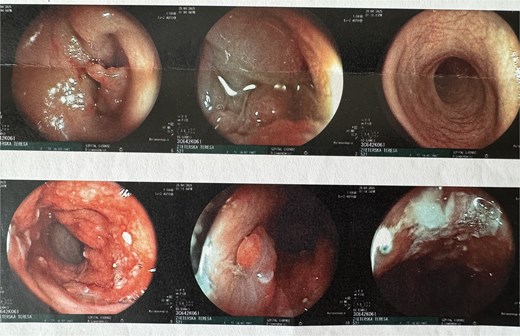

A colonoscopy was subsequently performed, which revealed, at ~40 cm from the anal verge, a concentric infiltrative lesion significantly narrowing the intestinal lumen (Fig. 3). An attempt to advance the endoscope resulted in bleeding. Additionally, signs of proctitis were noted. Histopathological examination confirmed a moderately differentiated (G2) adenocarcinoma of the colon.